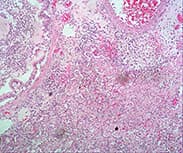

蘇木素-伊紅 (HE染色) |

大多數(shù)組織 | 組織學(xué)、胚胎學(xué) | ![]() |